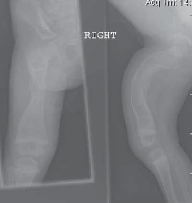

Chapter 51 Radial Dysplasia Reconstruction Scott N. Oishi and Marybeth Ezaki DEFINITION Radial dysplasia repr…